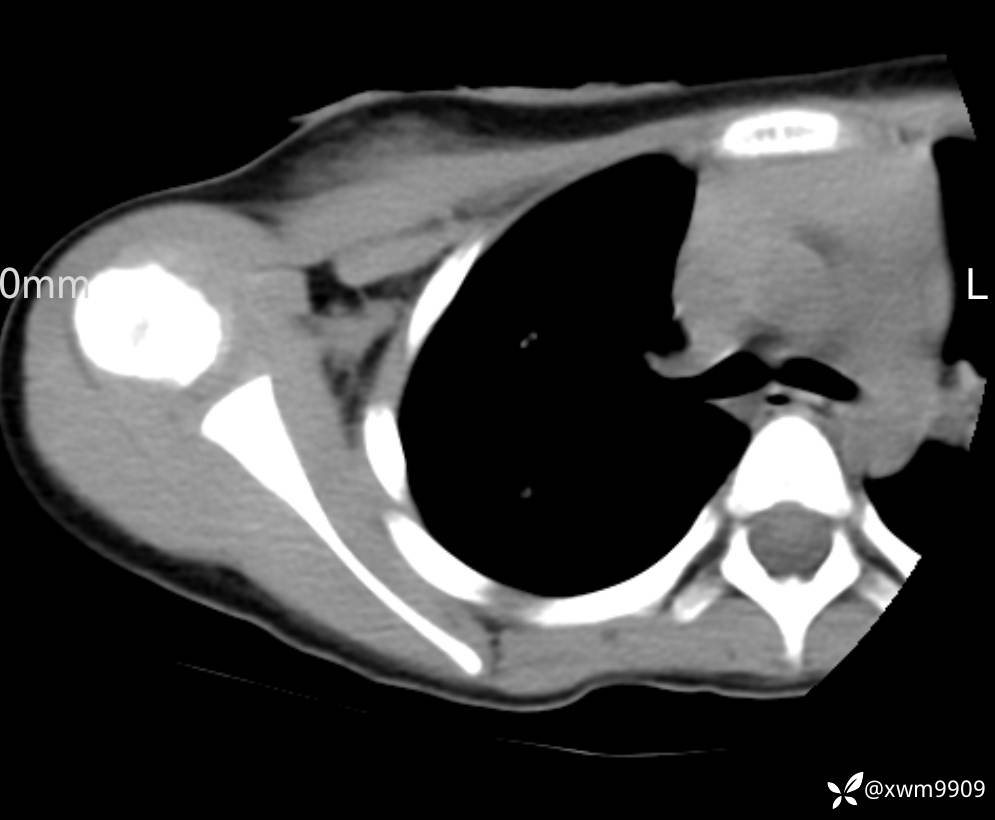

CT:

3、查体,右锁下方可及一约5x6Cm肿物,软丶边清丶未见明显发红,肤温不高,压痛明显,不可推动,稍有波动感。其他无特殊。

2024-03-20,女,6岁。因“发现右侧胸部肿物伴疼痛1天”入院。